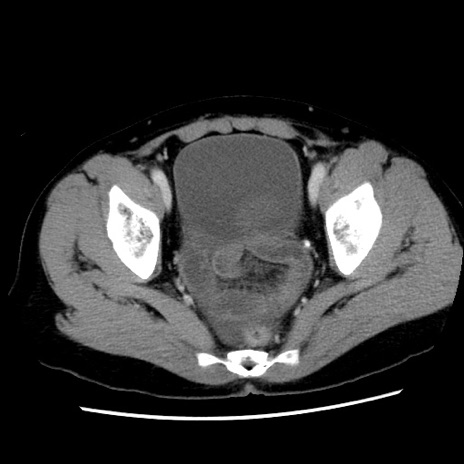

症例10(横断像)

【症例】 50歳代女性

【主訴】 腹痛

【現病歴】前日生レバーを食べた。今朝に排便あり。 昼前に突然発症の腹痛を生じ、当院救急外来を受診した。

【既往歴】 子宮筋腫にてで子宮全摘後

【身体所見】 意識清明、腹部:平坦、軟、下腹部やや左を中心に圧痛・反跳痛あり、筋性防御あり

【データ】WBC 7800、CRP 0.07